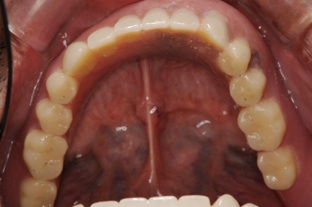

前歯しか残らなかった方です。奥歯にインプラントをしなければならないのですが、普通のインプラント治療であればサイナスリフト(骨移植)して1年待ってそれからインプラントを埋入してと1年半くらいかかってしまいます。ですが、オールオンフォーの治療を行っている医院であればこのような治療を施すことが可能となります。

この方は結局、all on 4 を応用し、奥歯に両側2本のインプラントを傾斜埋入して、それにマグネットをつけました。これなら骨移植をせずにインプラントが可能になり、3ヶ月ほどで終了できます。

マグネットをつけているので大幅に義歯の面積を縮小することが可能になりました。